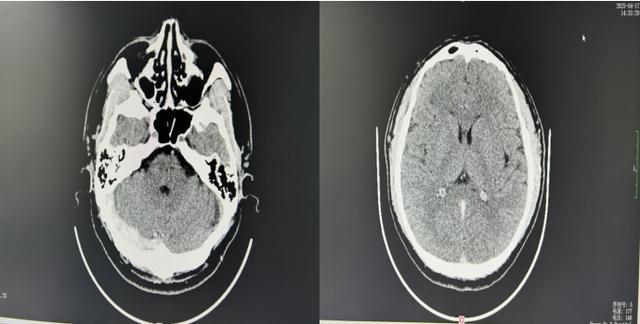

(▲4月17日颅脑CTA影像片)

3.诊断:影像学是关键

MRI联合MR静脉成像(MRV):无创且敏感度达95%,可清晰显示静脉窦充盈缺损。

CT静脉造影:适用于急诊,快速评估血栓位置。